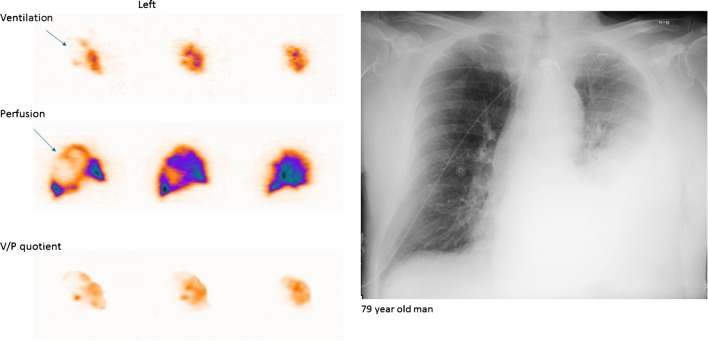

Immagini di perfusione (in alto) e ventilazione (in basso) in proiezione obliqua posteriore destra, che mostrano difetti a cuneo in un paziente con EP.